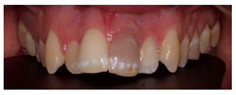

In this scenario, the participants were asked to select the most adequate treatment option for the treatment of the carious lesions present in teeth 1.3, 1.2, 1.1, 2.1, 2.2, and 2.3. The most prevalent answer for teeth 1.3, 1.1, 2.1, and 2.3 (94.2%) was “remineralization” (clinical scenario 5a), which was the correct answer. For tooth 1.2 (clinical scenario 5b), the most prevalent answer was “root canal treatment” (51.2%), followed by “restoration with resin composite” (22%). For tooth 2.2 (clinical scenario 5c), the most popular option was “restoration with resin composite” (85.4%), followed by “remineralization” (22%). The correct answer for teeth 1.2 and 2.2 was “restoration with resin composite” (Figure 1).

The majority of students coincided with the available protocols for approaching active carious lesions limited to enamel (clinical scenario 5a). However, when lesions extended to dentin (clinical scenarios 5b and c), the therapeutic alternatives were more discordant. Specifically, for the treatment of tooth 1.2, in which the extension of the carious lesion surpassed the external third of the dentin, 51.2% of the students proposed a root canal treatment, which is considered as an overtreatment in this case [35].